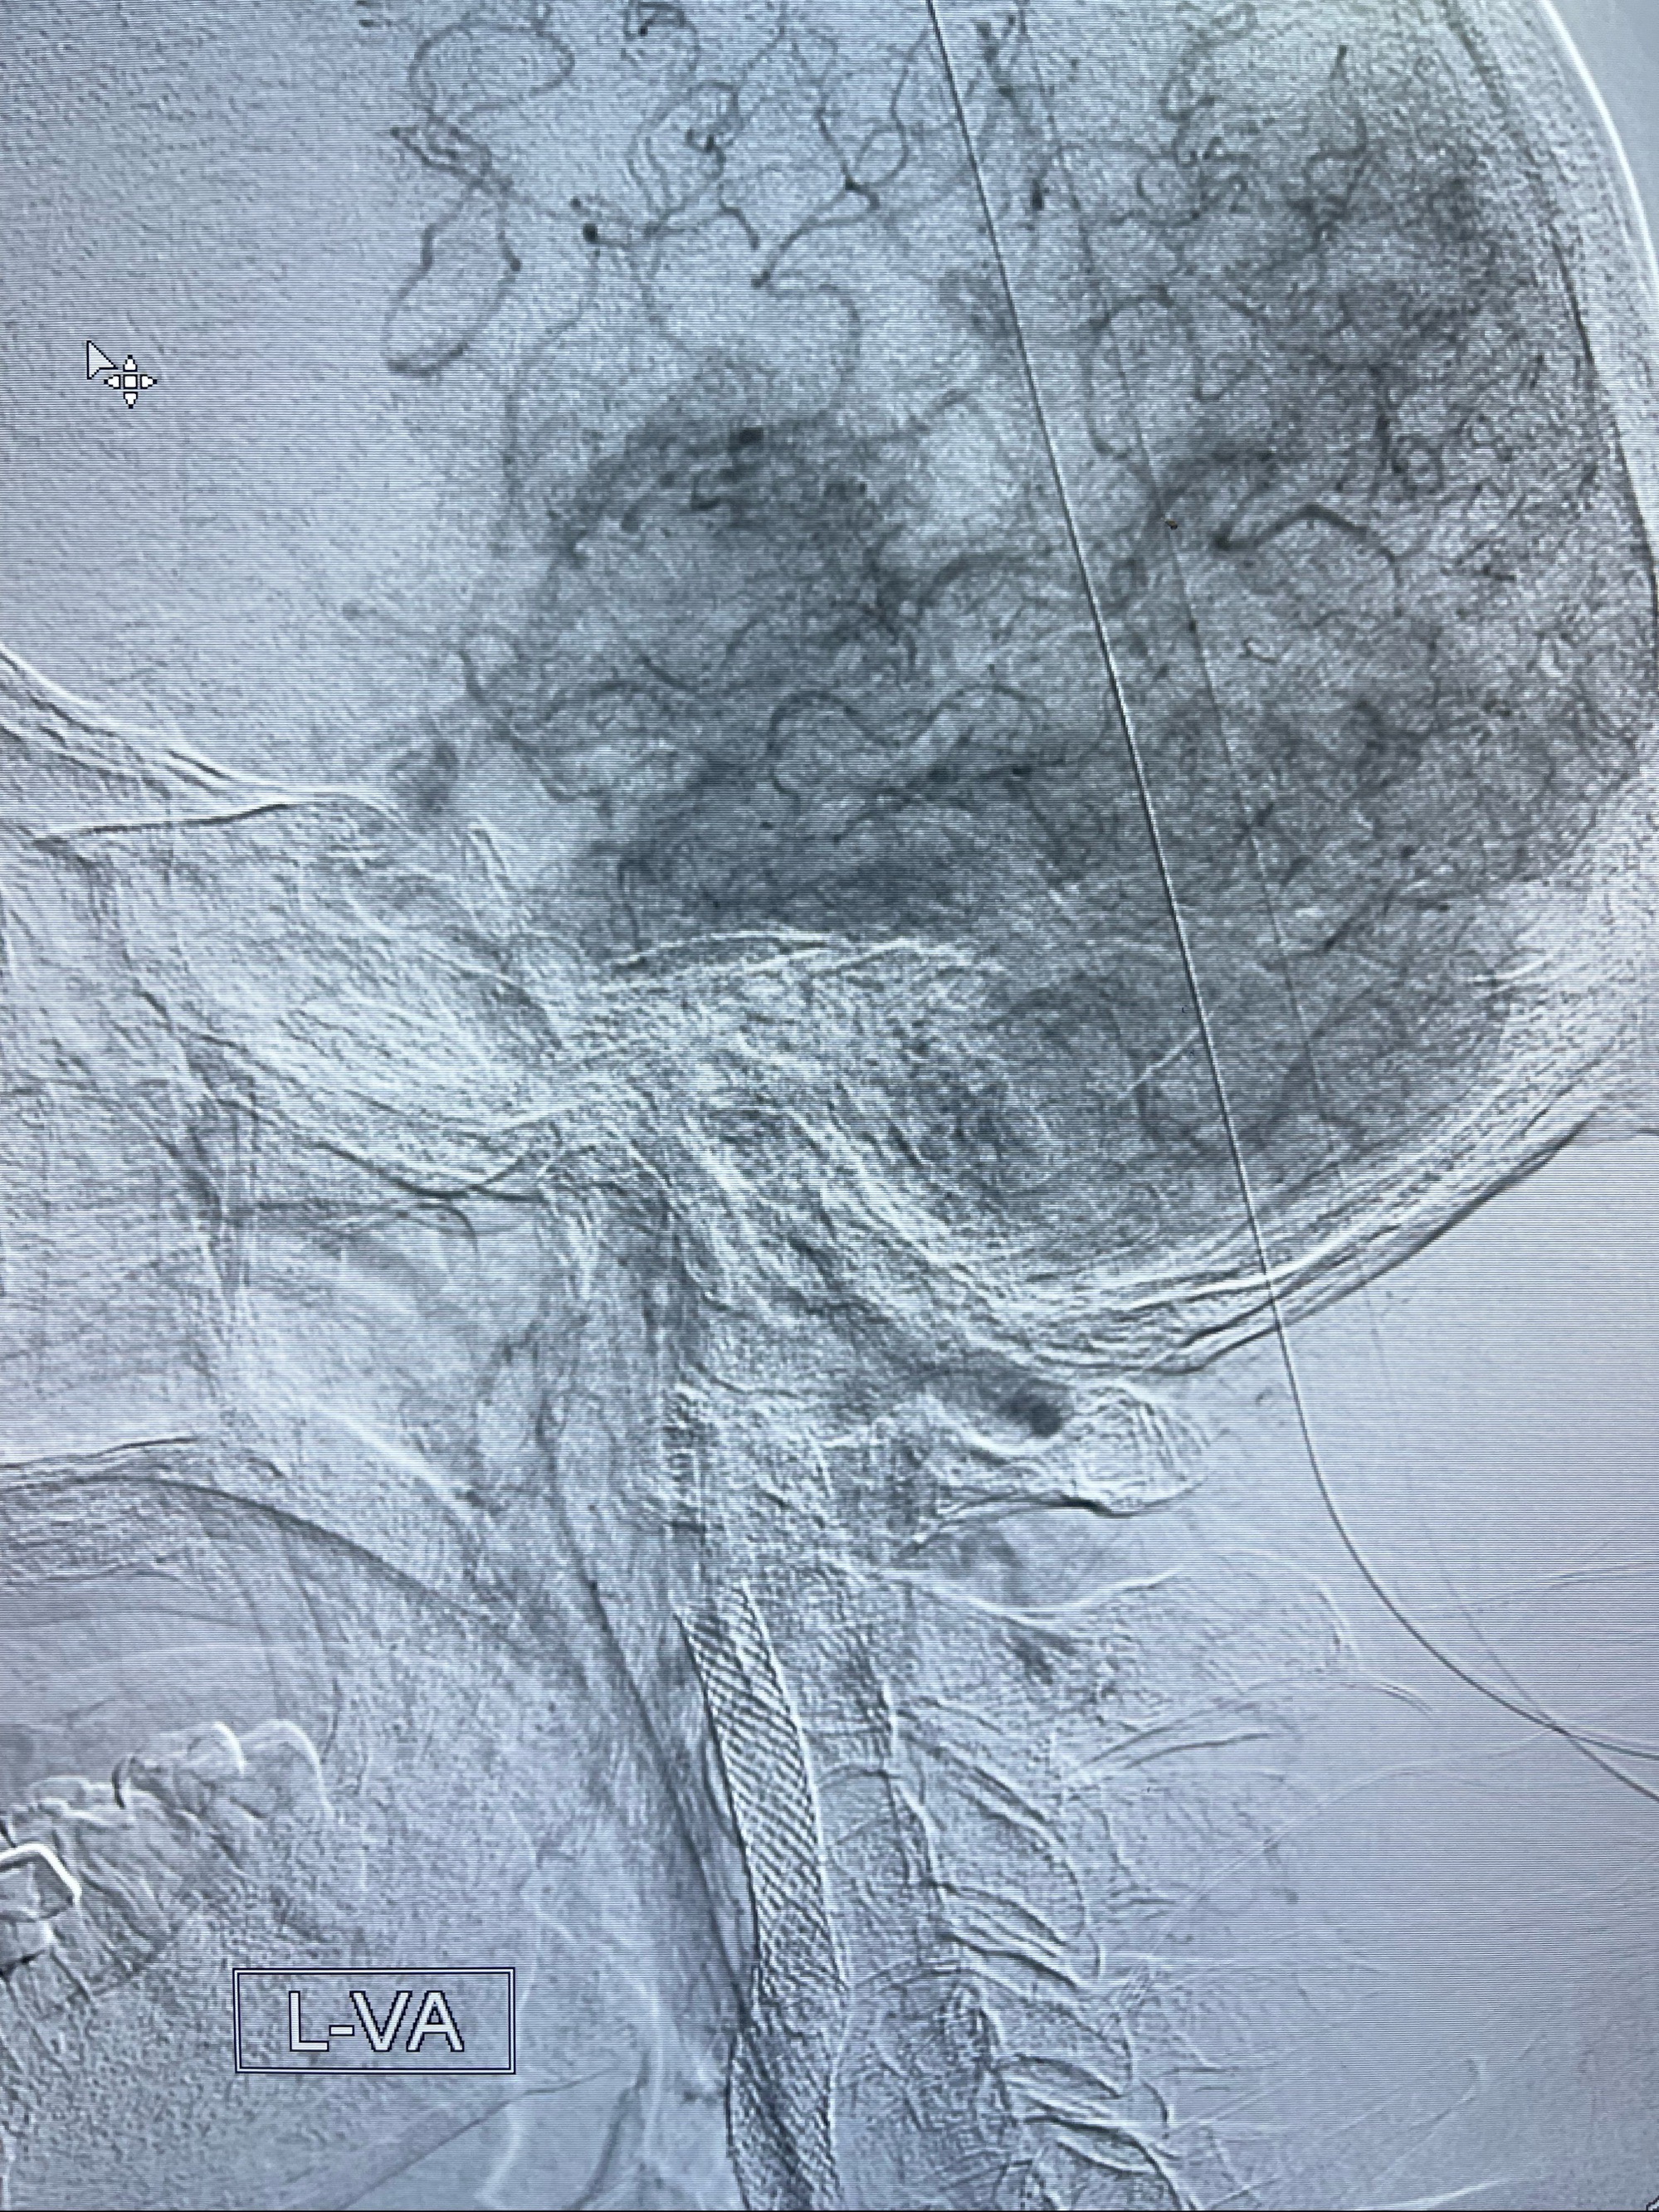

2023-07-10DSA:右侧颈内动脉岩骨段夹层伴中偏重度狭窄改变,左侧颈总动脉闭塞、右侧颈外动脉由右侧肋颈干甲颈干吻合代偿

箭头所示为颈内动脉岩骨段重度狭窄,结合MRI,考虑为肿瘤侵犯右侧颈内动脉

箭头以近至支架段管腔不规则狭窄

右侧椎动脉可见吻合代偿右侧颈外动脉

左侧颈总动脉起始段至分叉部闭塞,起始部呈现子弹头样改变

左侧椎动脉可见代偿显示左侧前循环